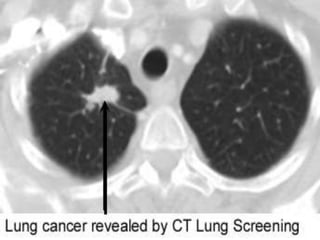

• 26.

IMAGING • All patientswith suspected NSCLC should undergo contrast-enhanced computed tomography (CT) that extends through the lungs, liver, and adrenal glands. CT is ideal for tumor node metastasis (TNM) staging • It can characterize the primary tumor and define its relationship to the chest wall and mediastinal structures • It can identify mediastinal lymph nodes that are enlarged and suspicious for malignant involvement • It can detect contralateral lung, chest wall, or upper abdominal lesions that are suspicious for metastasis